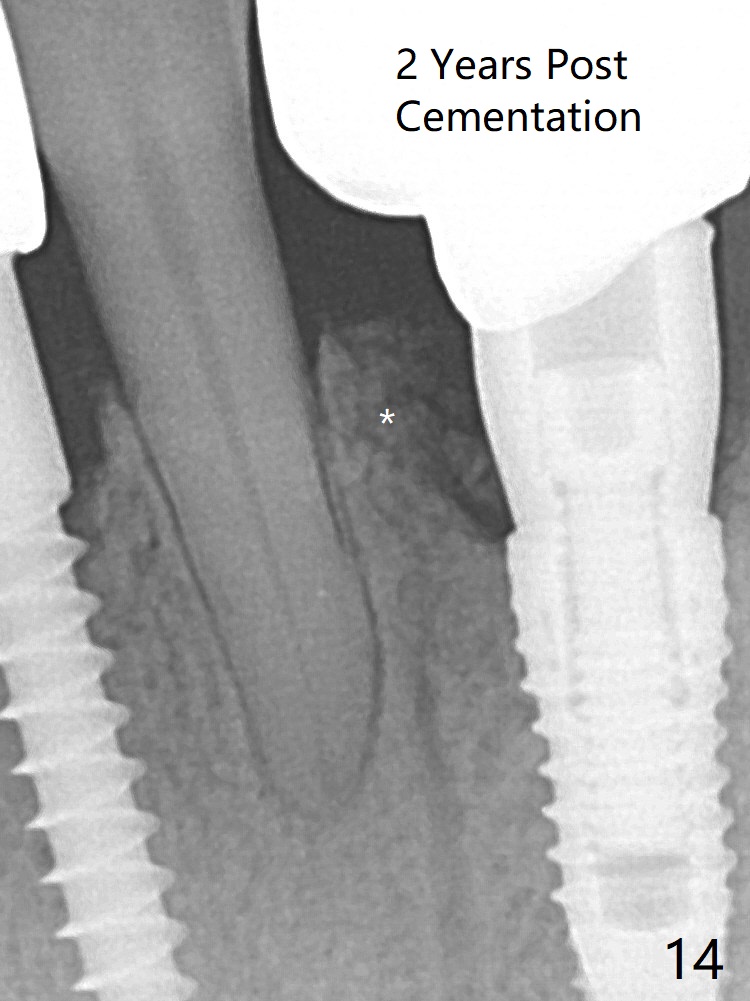

A 3.8x10 mm dummy implant is placed tentatively with an apical space (Fig.4 (the distal root surface of the lateral incisor is denuded (<)). When a same dimension definitive implant is placed with 40 Ncm, it is 2 mm below the lingual gingival margin, whereas 6-7 mm below the buccal one (Fig.5). Vanilla graft is placed before placement of a 5.5x4(5) mm abutment (Fig.6). The root surface of the lateral incisor is covered by the bone graft. Later the abutment is changed to a longer and smaller one (Fig.8) with more of the allograft (*). The short implant is chosen because it has to be placed deep to prevent periimplantitis, especially lingually, in spite of the fact of the unfavorable crown/implant ratio (Fig.4). The diameter of the implant is small so that there is ample space to pack bone graft both buccally and lingually. The majority of the bone graft seems to be in place 8 months postop (Fig.12). The ridge completely regenerates 2 years post cementation (Fig.14).